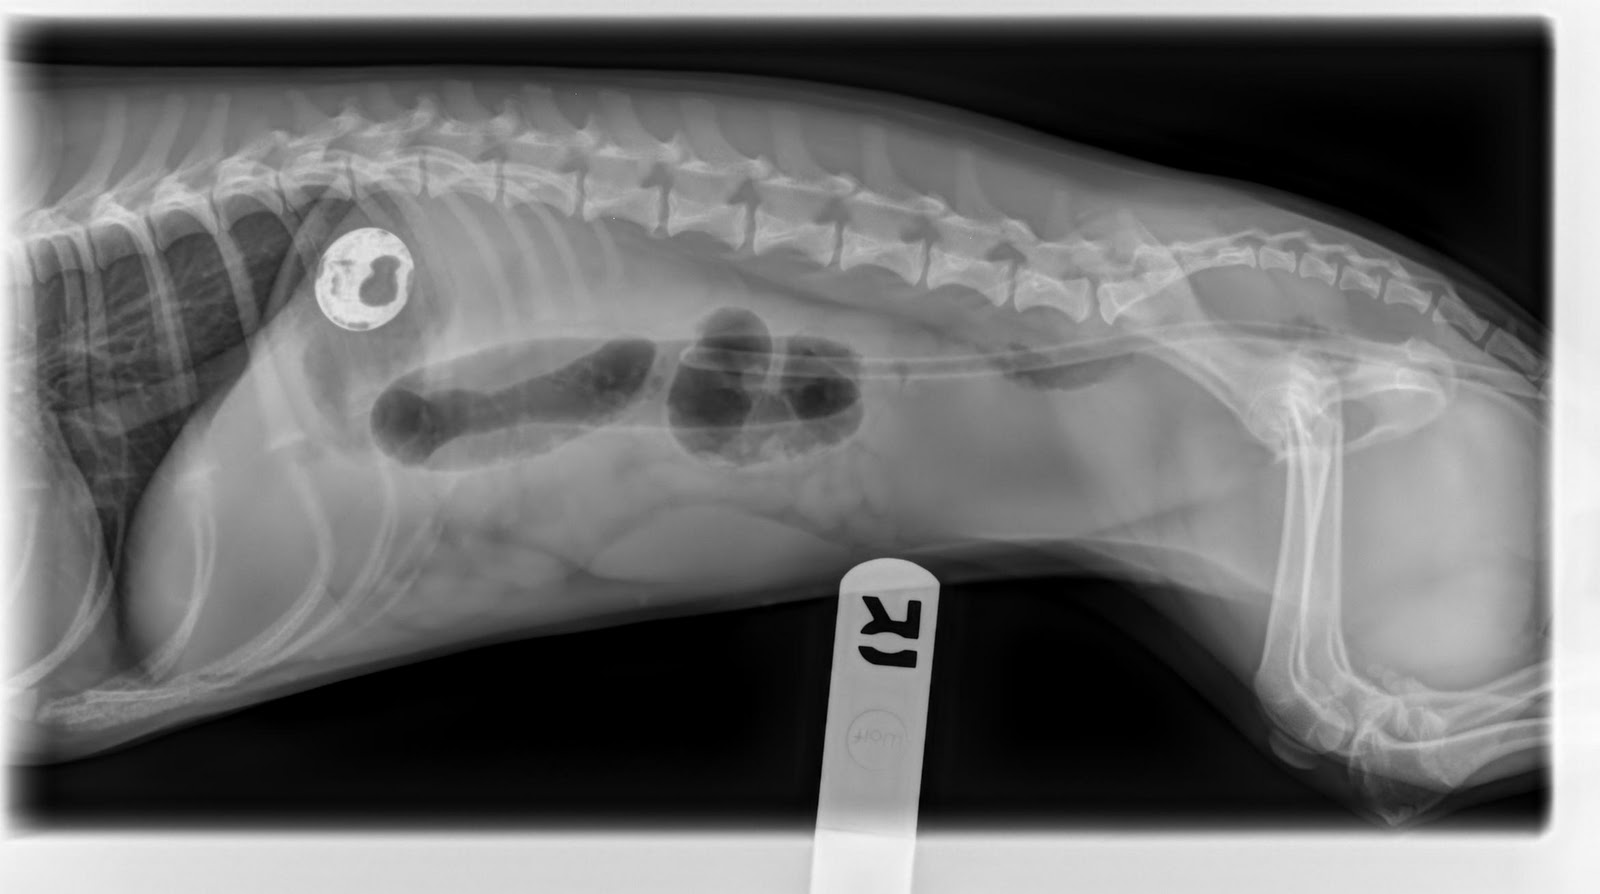

Dog Zinc Poisoning . When canines ingest certain types of zinc, there is a formation of. Gross pathologic findings in dogs and cats include nonspecific hepatomegaly; Symptoms of zinc toxicosis include appetite loss, vomiting, diarrhea, lethargy, and collapse. Acute zinc poisoning is a relatively common source of poisoning in dogs. And inflammation, edema, or ulceration of the gi mucosa. Here are a few signs to notice. It is most common in pet dogs, possibly because of their indiscriminate eating habits. Ingestion of metal objects containing zinc or high dietary levels of zinc cause the more classic clinical signs of zinc toxicosis (eg, intravascular hemolysis). Zinc poisoning in dogs is common and can be treated effectively if owners recognize early symptoms after ingestion. Ingested metal objects show up. Zinc toxicity has been seen in a wide range of animals.

Symptoms of zinc toxicosis include appetite loss, vomiting, diarrhea, lethargy, and collapse. Acute zinc poisoning is a relatively common source of poisoning in dogs. And inflammation, edema, or ulceration of the gi mucosa. Zinc toxicity has been seen in a wide range of animals. Ingested metal objects show up. Zinc poisoning in dogs is common and can be treated effectively if owners recognize early symptoms after ingestion. It is most common in pet dogs, possibly because of their indiscriminate eating habits. Gross pathologic findings in dogs and cats include nonspecific hepatomegaly; Here are a few signs to notice. Ingestion of metal objects containing zinc or high dietary levels of zinc cause the more classic clinical signs of zinc toxicosis (eg, intravascular hemolysis).

Dog Zinc Poisoning Here are a few signs to notice. Ingested metal objects show up. When canines ingest certain types of zinc, there is a formation of. Symptoms of zinc toxicosis include appetite loss, vomiting, diarrhea, lethargy, and collapse. Acute zinc poisoning is a relatively common source of poisoning in dogs. Ingestion of metal objects containing zinc or high dietary levels of zinc cause the more classic clinical signs of zinc toxicosis (eg, intravascular hemolysis). And inflammation, edema, or ulceration of the gi mucosa. Zinc toxicity has been seen in a wide range of animals. It is most common in pet dogs, possibly because of their indiscriminate eating habits. Here are a few signs to notice. Gross pathologic findings in dogs and cats include nonspecific hepatomegaly; Zinc poisoning in dogs is common and can be treated effectively if owners recognize early symptoms after ingestion.